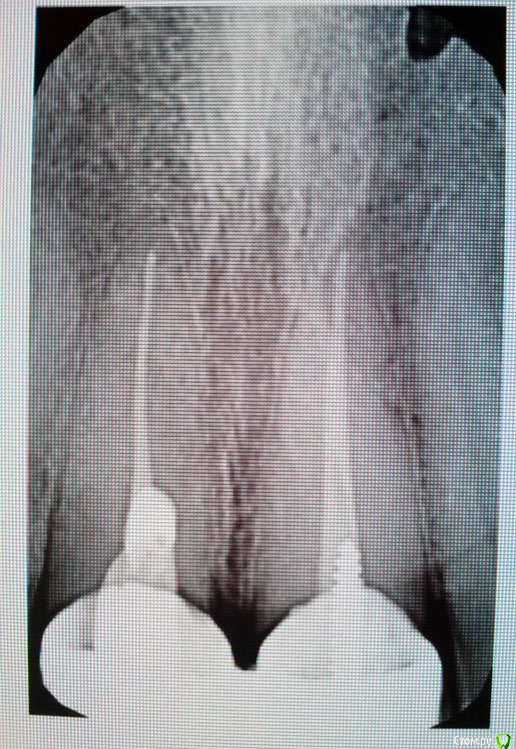

Dmitriy_ Опубликовано 28 июля, 2016 Автор Поделиться Опубликовано 28 июля, 2016 (изменено) Добрый день! КТ лучше сделать, т.к. оно очень мжет помочь при принятии решения имеет ли смысл перелечивать каналы. Скажите пожалуйста, это касается только верхней 6-ки слева? Или резцов это тоже касается? В Пикассо (это сеть диагностических центров) можно нужную область на картинке выделить.Есть прицельный снимок резцов (прикладываю). Касательно резцов о чем идет речь, возможно даже удаление понадобится? Зуб мудрости вверху слева нужно удалить. Это сложное удаление? Т.е. нужно искать доктора для которого это рутина? Или терапевт который будет перелечивать зубки с этим справится? Зуб прорезался, смотрит в направлении щеки градусов на 40. Я щеткой еле достаю... St., спасибо большое за Ваш ответ! К модераторам: Я наверное ошибся разделом, в терапию нужно было? Изменено 28 июля, 2016 пользователем Dmitriy_ Ссылка на комментарий

St. Опубликовано 28 июля, 2016 Поделиться Опубликовано 28 июля, 2016 Скажите пожалуйста, это касается только верхней 6-ки слева? Или резцов это тоже касается? И тех, и других. Сегмент не получится сделать, т.к. зубы далеко и в один снимок не влезут. Тем более Вы ещё и имплантацию внизу планируете. Проще делать обе челюсти, чтоб было видно всё. Касательно резцов о чем идет речь, возможно даже удаление понадобится? Скорее всего нет. Вопрос в наличиии воспаления за пределами корня и необходимости перелечивания каналов. 1 Ссылка на комментарий